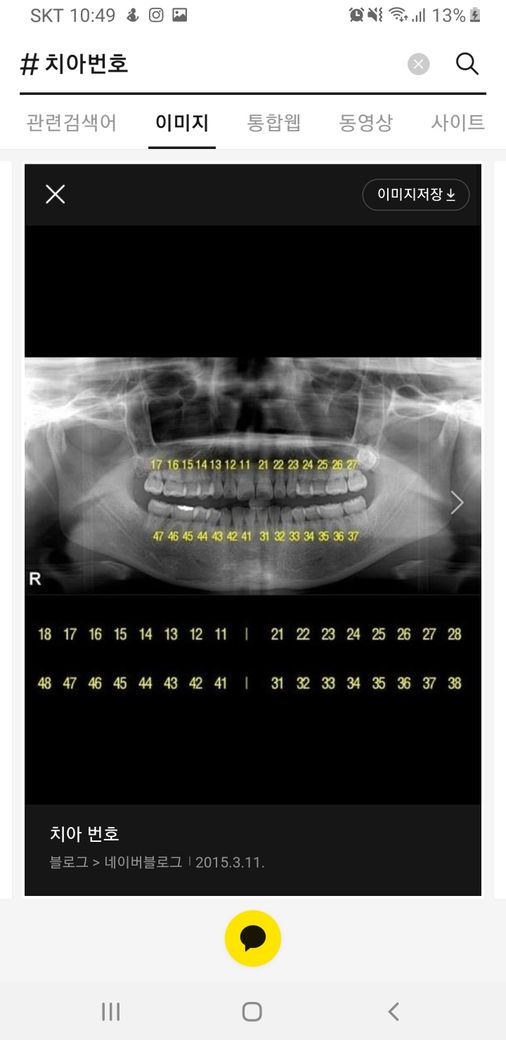

상악우측 제1대구치는 #16번 치아를 의미합니다. 파노라마 사진상에서는 왼쪽위에 여섯번째 치아를 의미해요

치아번호로 #16번 치아입니다.

상악우측제1대구치라면, #16번 치아를 의미하는 것입니다.

상악 우측 제1 대구치는 질문자님이 올려주신 파노라마 상에서는 17번에 해당합니다. 따라서 본인 기준으로 했을때는 오른쪽 맨 뒤 치아 앞에 치아를 말합니다. 치관 1/4 위치라는 것은 치아 머리 위에서 1/4 되는 지점이라고 생각하시면 됩니다. 감사합니다.